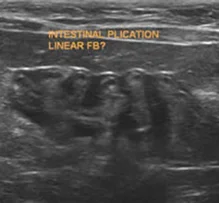

Soft Tissues

The advanced diagnostic technique of ultrasound has become a standard of care in veterinary medicine allowing the practitioner the opportunity to opt for less invasive testing.  The speed and accuracy of results frequently outweigh the client & patient stress, expense, and pain of more invasive diagnostics and surgery. When combined with various minimally-invasive biopsy techniques, a diagnosis can be safely and accurately determined in most cases.  Conversely when based on ultrasound findings, the practitioner can be confident that more aggressive (and often necessary) procedures such as exploratory laparotomy are definitively indicated to further characterize or resolve a given problem.

• Abdominal exam – liver, gallbladder & biliary system, stomach, pancreas (especially now in cats), spleen, kidneys, adrenals, bladder, prostate, uterus, ovaries, bowel, vasculature, lymph nodes (mesenteric, hepatic, iliac), mesentery & serosal surfaces.

• All abdominal ultrasound exams are complete exams. It is dangerous practice to only examine part of the abdomen – all organs must be examined every time to ensure there is not occult pathology.